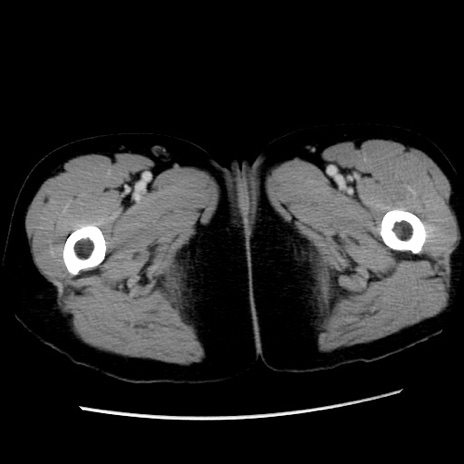

症例10(横断像)

【症例】 50歳代女性

【主訴】 腹痛

【現病歴】前日生レバーを食べた。今朝に排便あり。 昼前に突然発症の腹痛を生じ、当院救急外来を受診した。

【既往歴】 子宮筋腫にてで子宮全摘後

【身体所見】 意識清明、腹部:平坦、軟、下腹部やや左を中心に圧痛・反跳痛あり、筋性防御あり

【データ】WBC 7800、CRP 0.07